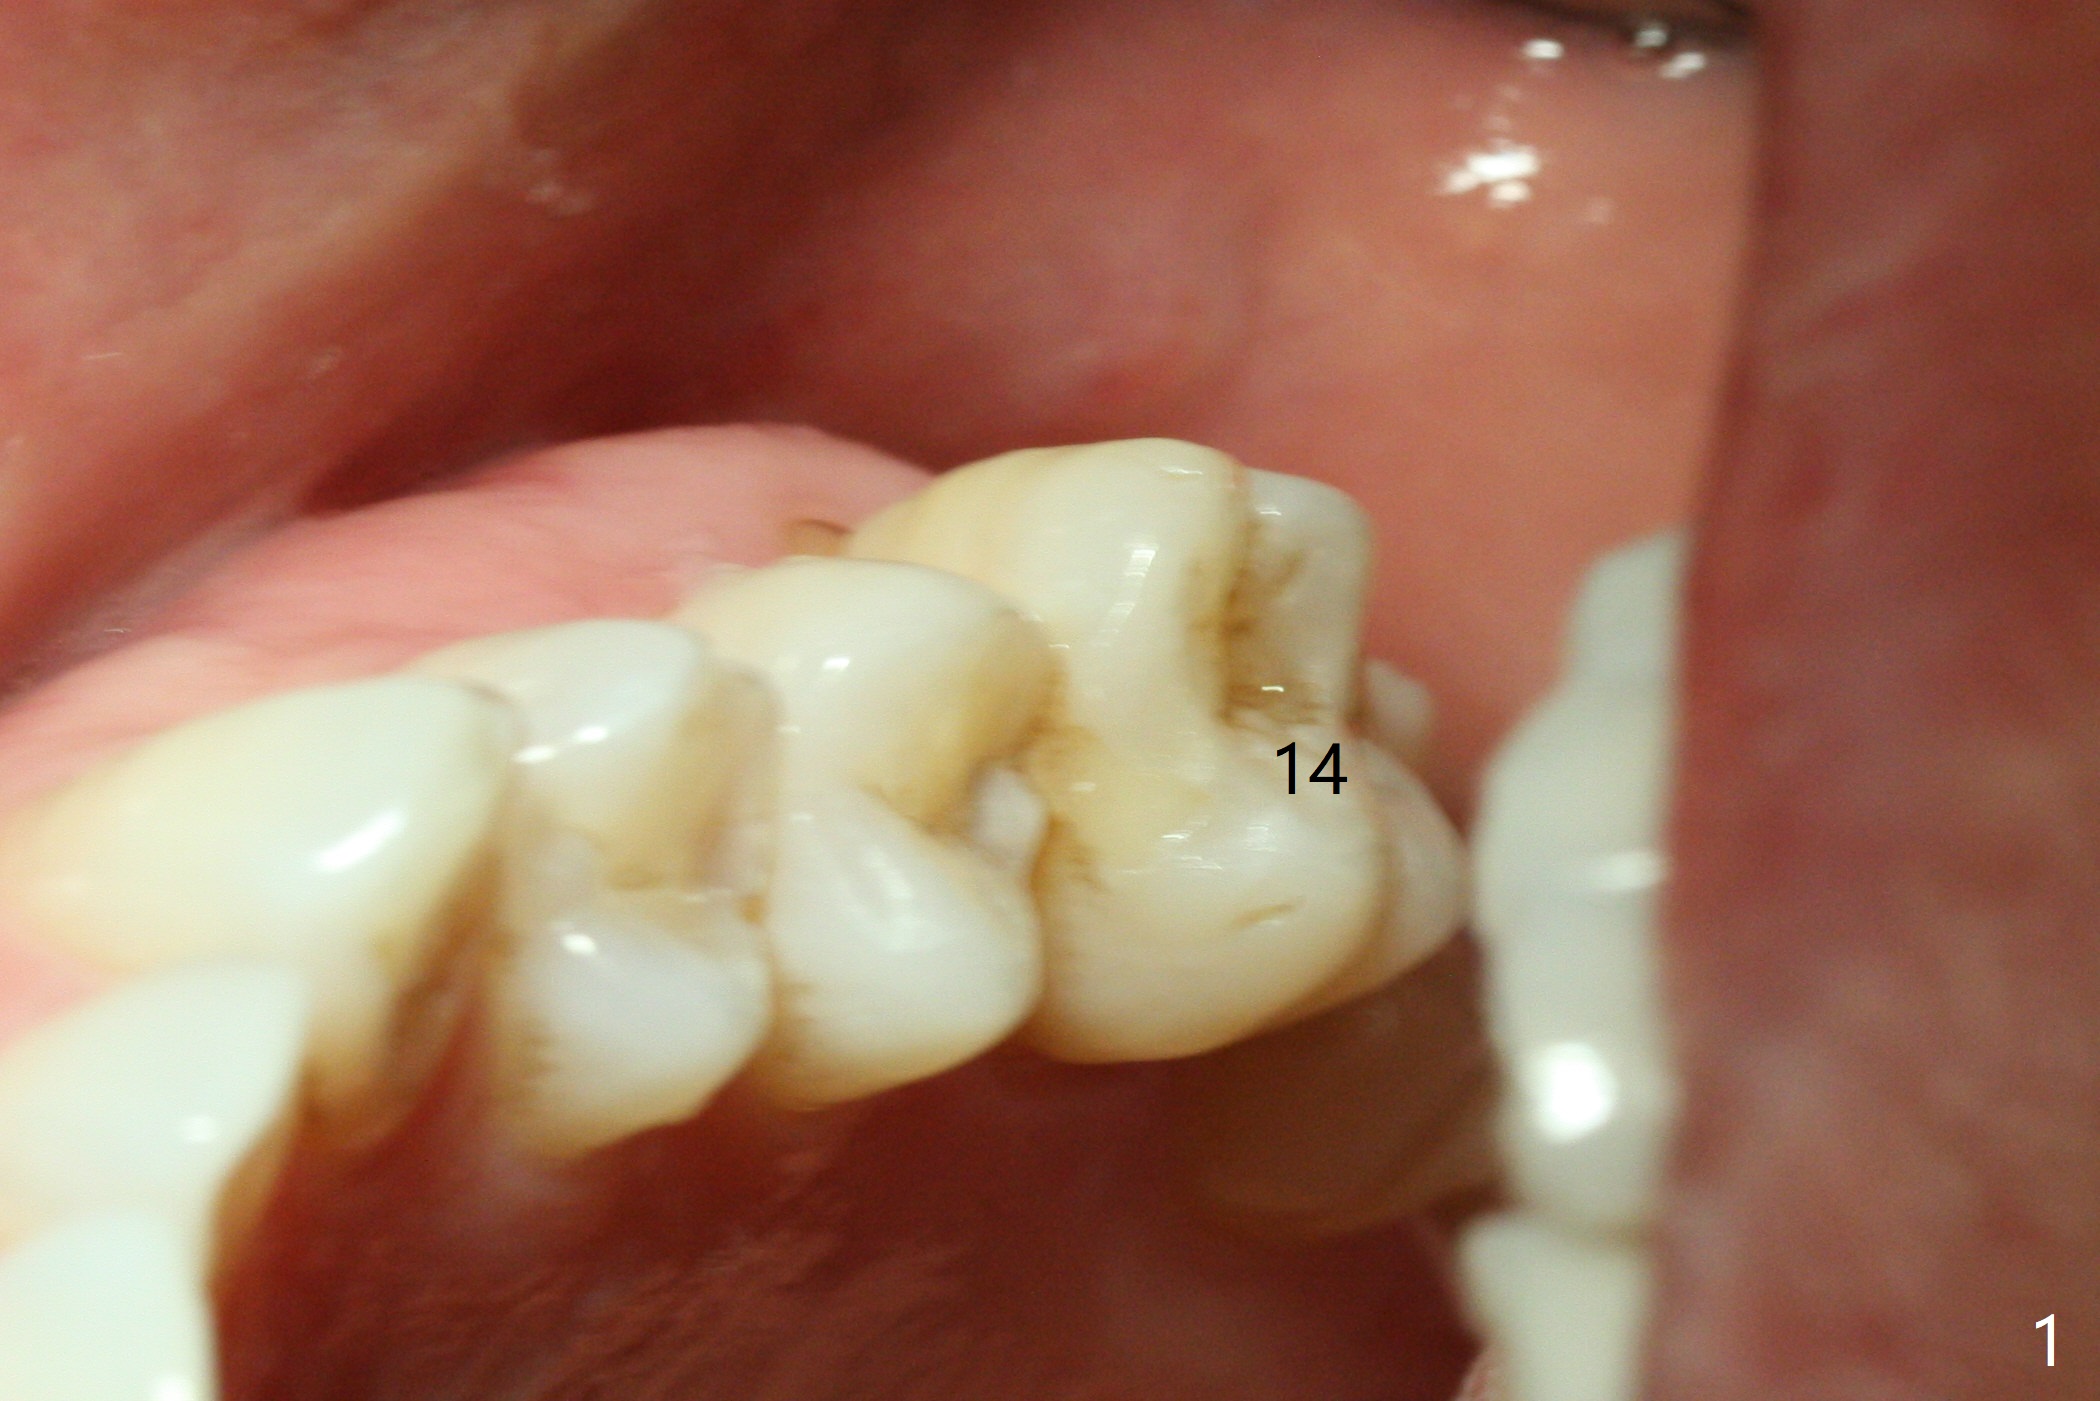

Fourteen days prior to implantation at #19 to replace a flipper (Fig.2), two minimplants are placed to intrude the supraerupted opposing tooth (#14, Fig.1). After use of minimal amount of local anesthetic (to keep proprioceptive in case root surface violation), the miniimplants are inserted ~ half of the length initially (Fig.3,4). The mesiobuccal (MB) one seems to be better positioned than the distopalatal (DP) one. When the implants are completely seated (Fig.5,6), three of PAs are taken, which suggests contact of the MB implant to the MB root of the tooth #14 (Fig.7 arrow). Immediately postop CT confirms approximation of MB and DP implants to the MB and P roots, respectively (Fig.8,9). The trajectory of these implants remain unchanged. Twelve days postop, the patient returns, uncomfortable with the palatal implant. After deep placement to bury the cuff (Fig.6) without local anesthesia (bone having no innervation), the patient feels better.